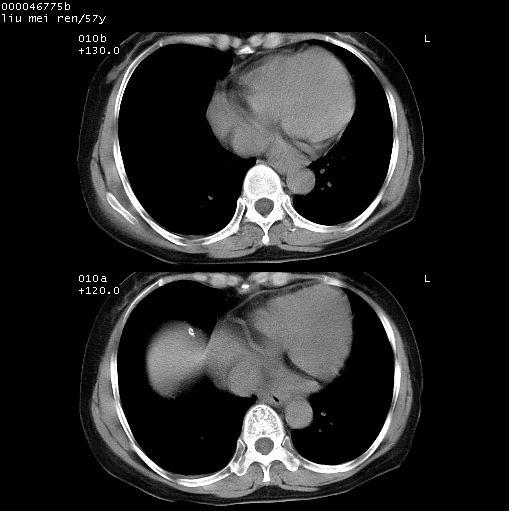

标题: CT12948:鉴赏一下——上腔静脉变异(CT平扫表现)。

患者 女,57岁。因车祸受伤,其家属要求行“全身ct检查”。平素健康。

胸部ct轴位平扫(层厚10mm,螺距1.5,重建间隔10mm),图像如下:

左位上腔静脉,先天变异。

左位上腔静脉,先天变异。与双侧上腔静脉区别。